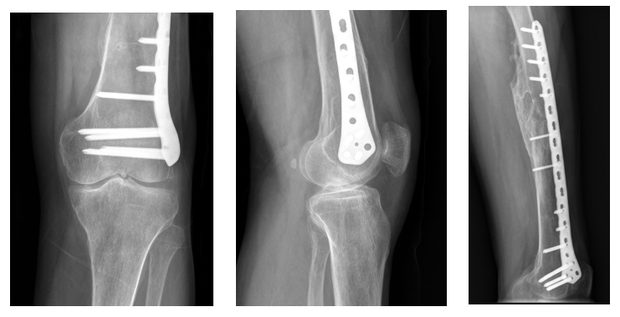

患者术前X-ray(显示关节间隙变窄、骨质增生)